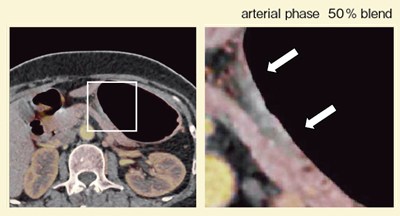

症例2は,体下部後壁小彎のUc型の早期胃がんで,病理診断結果は低分化腺癌であった。造影CTにて体下部後壁に浅い陥凹が認められ,動脈相でわずかに欠損が認められ,門脈相で濃染が回復し,平衡相で以前より良く濃染している様子が描出された。おそらく,生検やクリッピングにより,少し線維化が起こっているためと考えられるが,iodine imageを重ねると,50%ブレンドした画像(図6)では,四角で囲った部分では他の部分の粘膜が良く濃染しているにもかかわらず,粘膜の染まりはほとんど認められなかった。さらに,75%ブレンドした画像(図7)では,部分的な造影欠損が明瞭に認められ,低分化腺癌であることがCTで確実に診断できた。

![]() 図6 症例2:50%ブレンドiodine image |